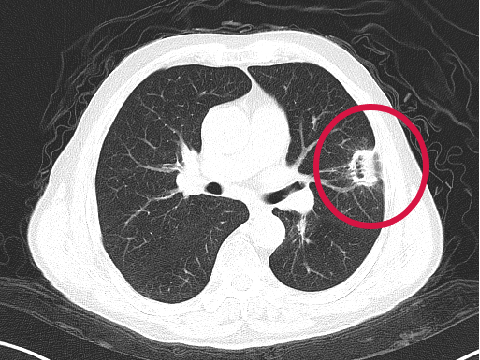

術(shù)后第1天

▲患者因體檢發(fā)現(xiàn)左肺上葉舌段結(jié)節(jié),考慮周圍型肺癌可能。因高齡、肺氣腫無法手術(shù),遂來院接受肺結(jié)節(jié)冷凍消融治療,術(shù)后病理為肺癌,定期隨訪提示腫瘤逐漸縮小。